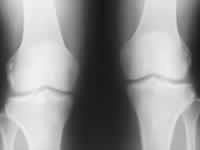

(上图为1列缺血性骨坏死SARS患者的膝关节片。X线平片无异常,MRI显示左侧股骨远端缺血性改变), http://www.100md.com